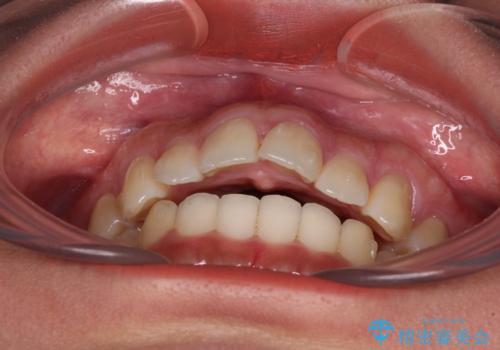

飛び出した上顎前歯 インビザラインで引っ込める

- 前歯の突出感を気にして来院された患者様です。

奥歯の咬み合わせは理想的な咬合に近く、インビザラインでも十分に対応できる歯列でした。

舌の突出癖を改善するためのトレーニングを行いつつ、上下歯列全体を後方に移動させ、更にはIPR(歯と歯の間を削る)によりスペースを獲得することで、口元の突出感を改善することとしました。

治療途中に上顎前歯が歯髄壊死を起こし、変色してしまいました。

痛みを感じたらすぐに連絡いただくよう伝えていましたが、忘れてしまっており、痛みと変色が発現したことで、すぐに連絡することを思い出されたとのことでした。

今後は、根管治療を行った後に、オールセラミッククラウンにて補綴治療を行う予定です。